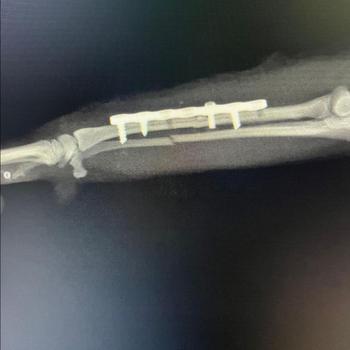

Bostanlı Sahil Veteriner Kliniği 10 Mart 2017 tarihinde İzmir Bostanlı’da Veteriner Hekim Burhan Gök ve Veteriner Hekim Rıdvan Akdağ tarafından hizmete açılmıştır. Kliniğimiz hasta karşılama bölümü , pet shop, muayene odası , donanımlı laboratuvar , ameliyathane ,yoğun bakım , karantina bölümü ,mutfak , traş ve banyo odasından oluşmaktadır. Sağlık söz konusu olduğunda hijyen ve ilginin önemini bildiğimiz için klinik şartları ve fiziki yapısı bu hususa özen gösterilerek hiçbir ayrıntı göz ardı edilmeden tasarlanmıştır . Sterilizasyonda gri yoktur. Siyah ve Beyaz vardır. Köklü geçmişi olan kliniğimiz Bostanlı'da yeni yerinde sizlere daha kaliteli hizmet vermeye hazır İzmir bölgesine hizmet veren tam donanımlı bir veteriner kliniğidir .Fiziksel muayeneler, endoskopik muayeneler, teşhis ve tedavi, laboratuvar hizmetleri, kısırlaştırma, aşılama, parazit kontrolü, mikroçipleme, diş temizliği ve bakımı, cerrahi operasyonlar, radyoloji, kan ve hormon analizleri ve daha fazlasını içeren ancak bunlarla sınırlı olmayan eksiksiz bir veterinerlik hizmetleri yelpazesi sunuyoruz. Hastalarımız için en kaliteli veteriner bakımı ve müşterilerimiz için olağanüstü müşteri hizmetleri sunmayı taahhüt ediyoruz. Veteriner hekimlerimiz ve personelimiz, evcil hayvanlarınızın evcil hayvanlardan daha fazlası olduğunu ailenizin bir parçası olduğunu bilir. Evcil hayvan sevenler ve evcil hayvan sahipleri olarak, dostlarımızın bizelere emanet olduğu bilincindeyiz kalite politikamız ve şeffaflık ilkelerimizle gurur duyuyoruz.